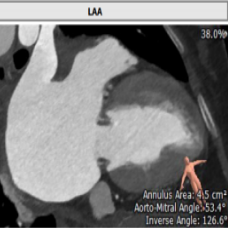

二尖瓣位评估

术前经详尽评估患者病情,通过CT重建测量瓣环直径、左室流出道面积。综合评估决定对该病例采用经静脉途径行二尖瓣“瓣中瓣”手术。既往植入25#St jude生物二尖瓣,测量支架内径22.9mm,选用23#SAPIEN 3球扩式瓣中瓣。虽手术过程异常艰难,但最终瓣中瓣植入位置理想,左室造影及经食道超声观察无明显瓣中及瓣周反流。瓣中瓣植入后观察左房峰值压明显下降,二尖瓣平均跨瓣压差降至3mmHg。